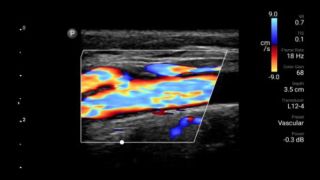

Lumify L12-4 broadband linear array transducer

From revealing the subtle details of an image to uncovering enriched tissue definition from multiple angles, Lumify can help you make real-time decisions with more confidence from assessment through recovery.